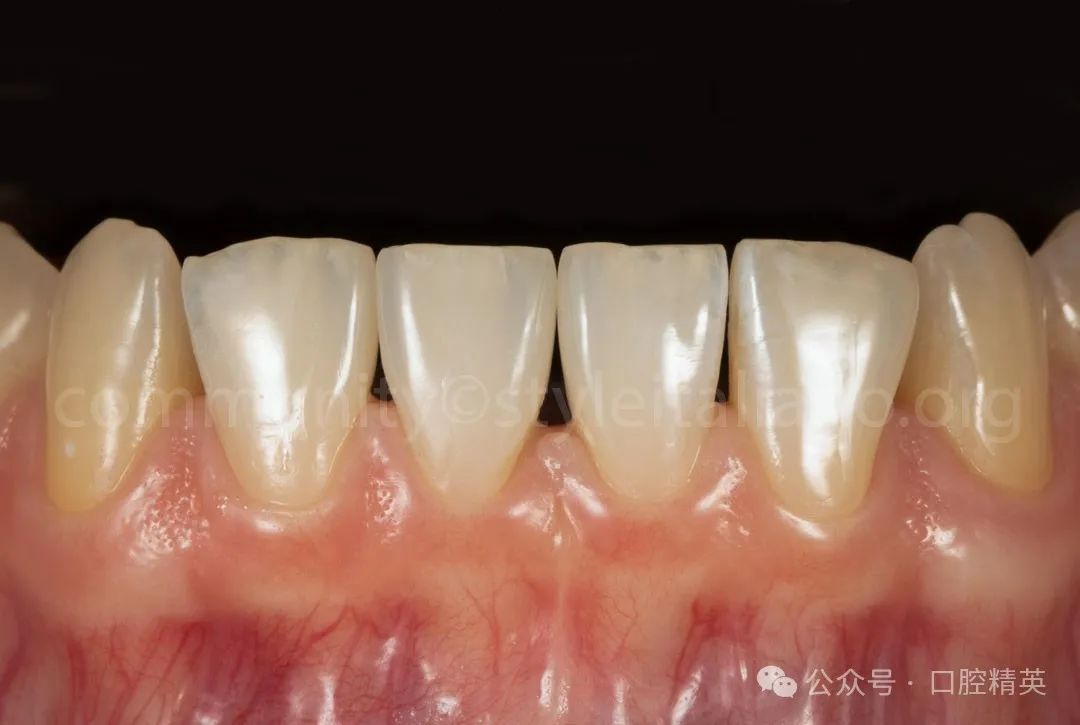

图10 修复后1周,修复体的最终外观显示出最佳的美学效果

修复后的牙齿呈现出自然、和谐的外观。这种方法保留了天然牙齿结构的完整性,促进了长期的口腔健康,并最大限度地减少了并发症的风险。利用CAD / CAM技术可以制作出高精度、个性化的修复体,而免预备技术可以减少患者的不适感和治疗时间。

这个案例突出了现代数字牙科如何在最小的干预下提供出色的功能和美学结果。